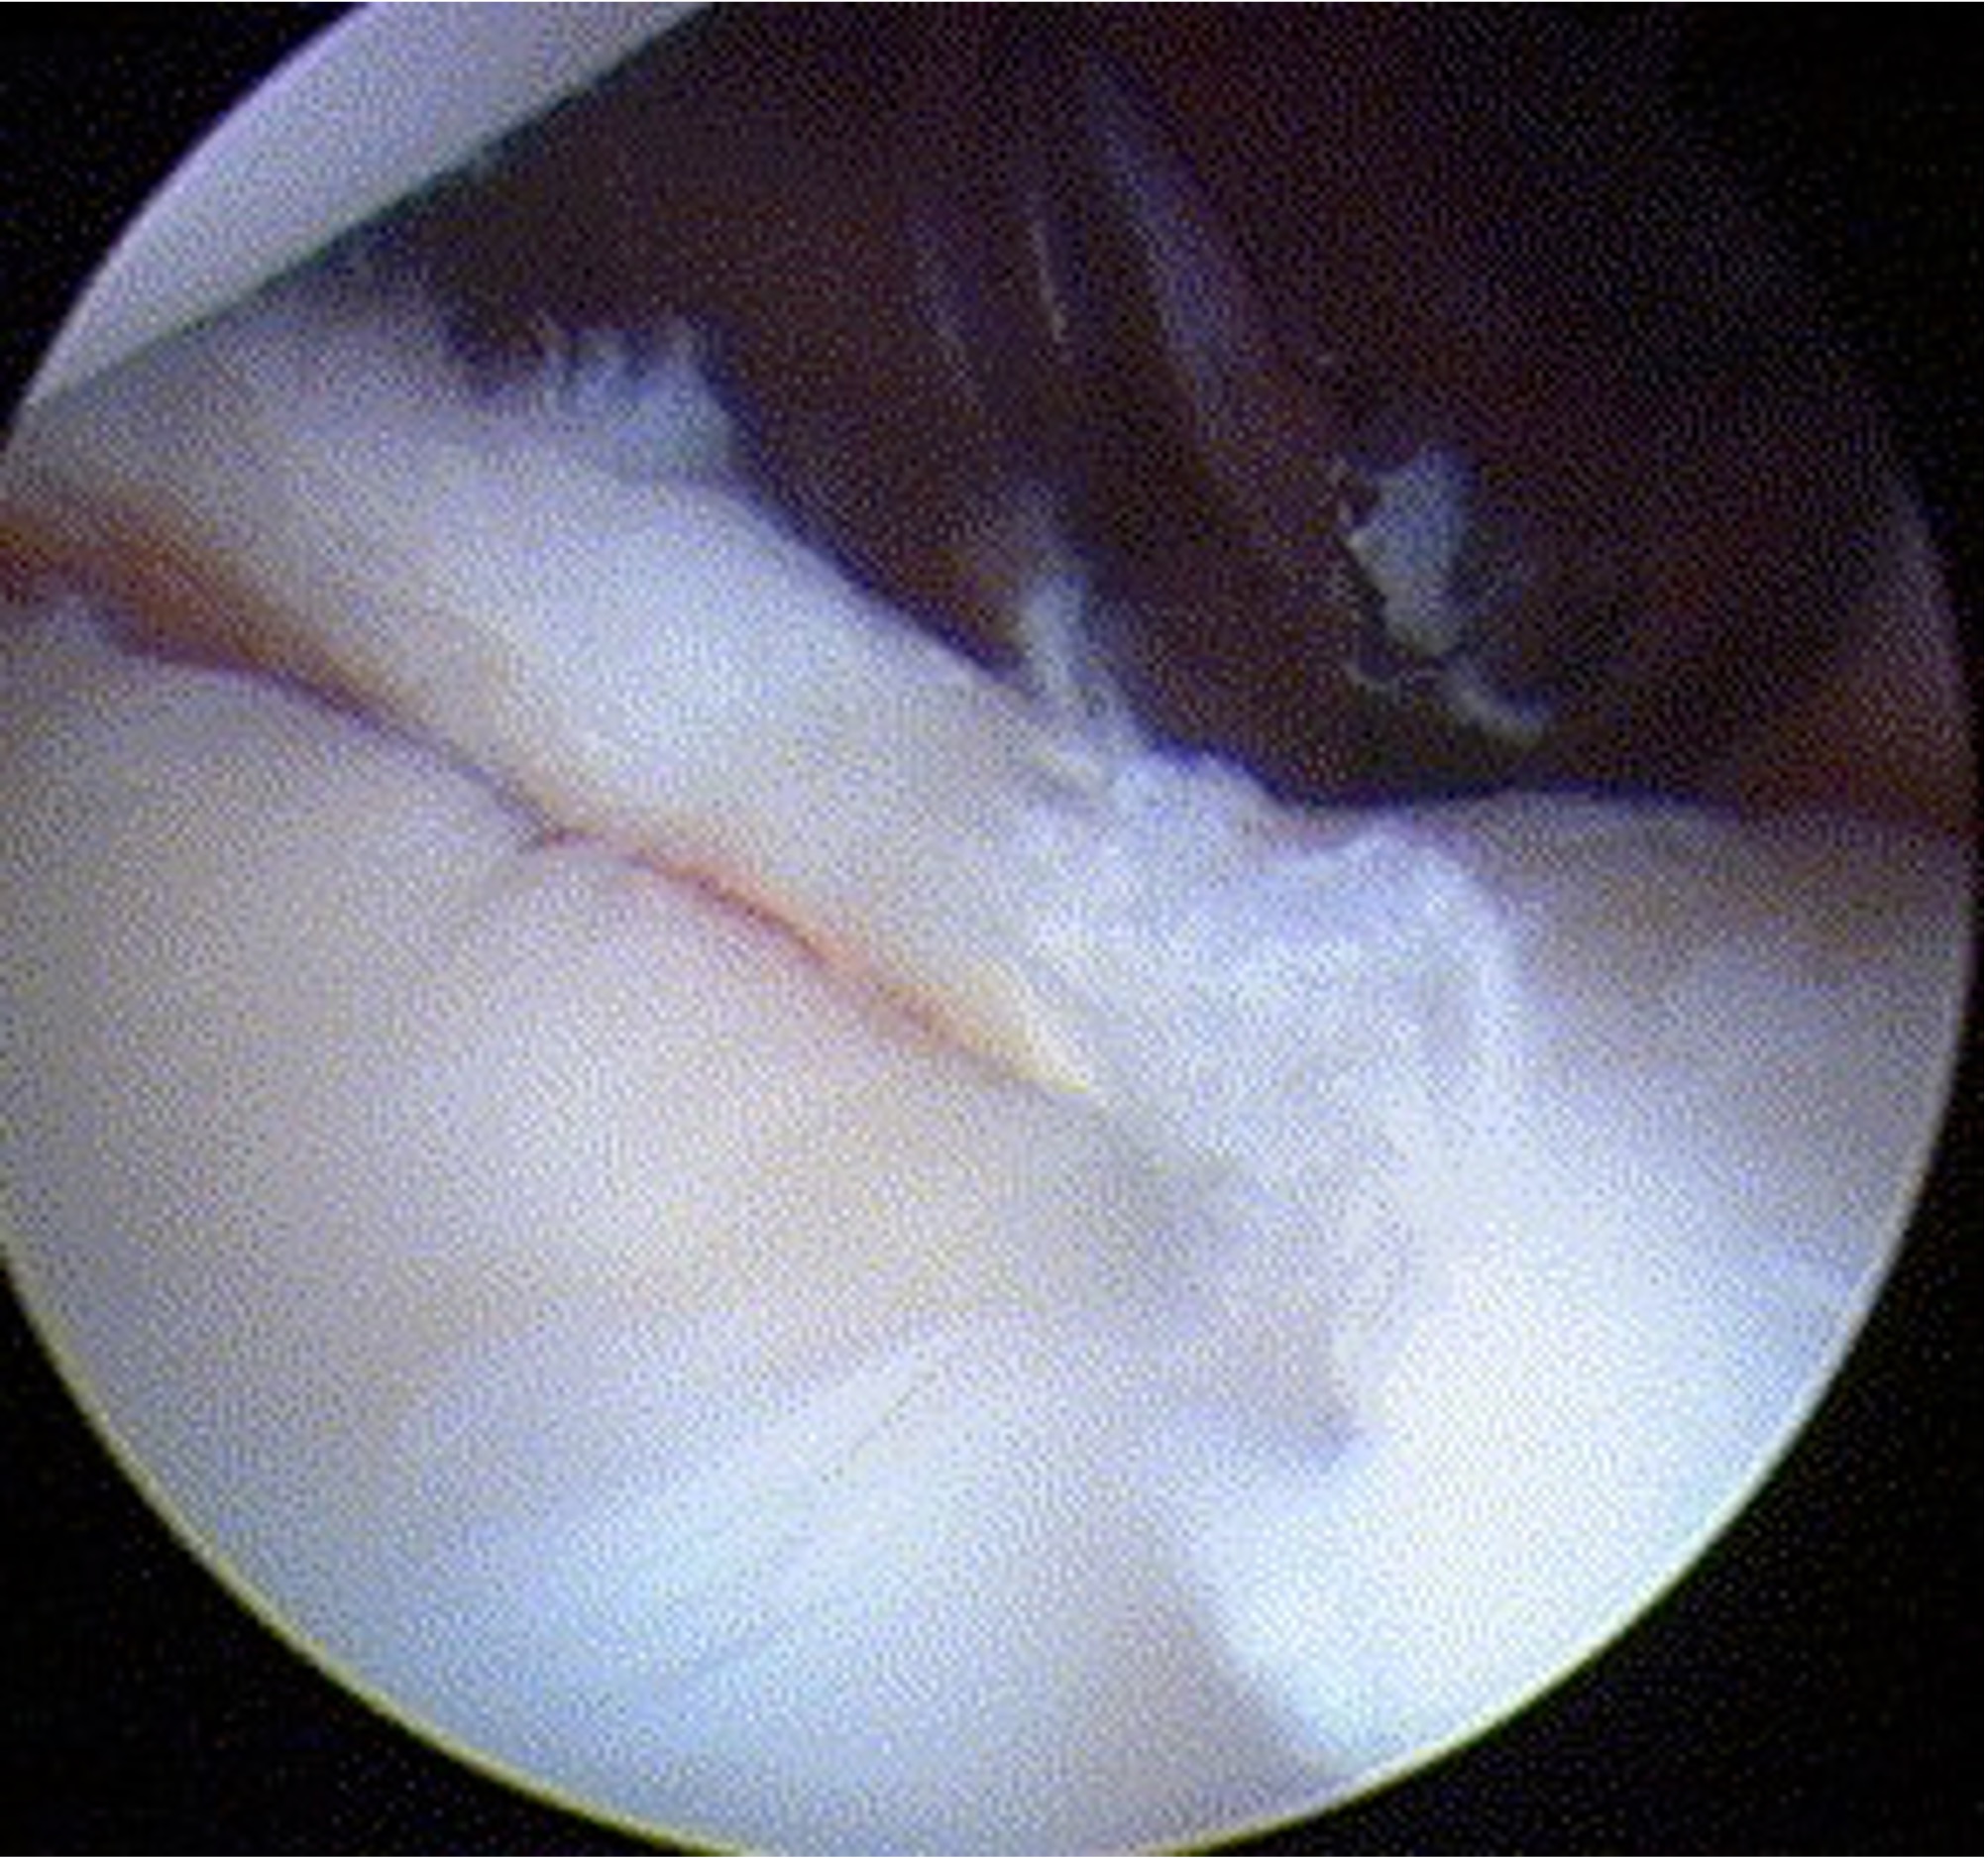

Debride anterior glenoid bone to bleeding bone

Pass sutures and tie knots

Typically curved suture passers

Aim to tighten capsule medially and superiorly onto glenoid